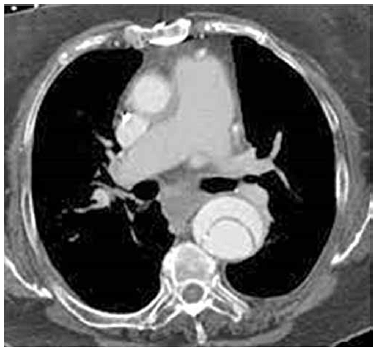

Homem, 60 anos, hipertenso, evolui com dor torácica em dorso de forte intensidade e início súbito, em caráter de facada. Realiza angiotomografia que evidencia a imagem a seguir. Frequência cardíaca de 90 bpm e pressão arterial de 240 x 120 mmHg.